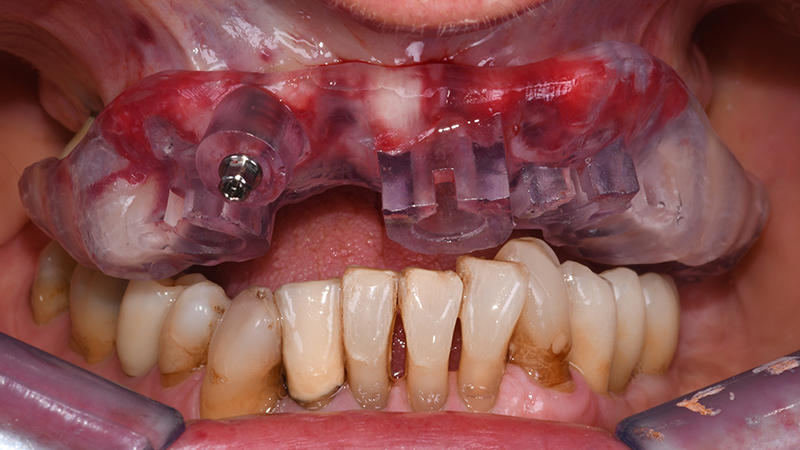

Dopo aver verificato la posizione della dima chirurgica sul modello digitale stampato, quest’ultima è stata posizionata in bocca tramite il supporto dentale dei settori latero-posteriori ed un pin di fissaggio è stato applicato (Anchor Pin Kit, Megagen, Daegu, Corea del Sud) (Figs. 7, 8, 9).

Fig. 8 - Visione frontale R2Guide® in situ dopo applicazione pin di fissazione

Fig. 9 - Visione occlusale R2Guide®

Le fixtures implantari sono state inserite seguendo il planning pre-chirurgico (Figs. 10, 11) in posizione 13-21-23-24. Lo spazio presente tra la componente vestibolare di ciascun impianto e l’osso vestibolare (jumping distance) e gli alveoli post-estrattivi non riceventi impianti, hanno ricevuto l’innesto di sostituto osseo xenogenico collagenato di origine suina (The Graft, Purgo, Challans, Francia) (Figs. 12, 13, 14) dopo aver posizionato i Multi-Unit abutment (MUA). La protesi provvisoria è stata avviata entro 24 ore dal termine della chirurgia (Figs. 15, 16).